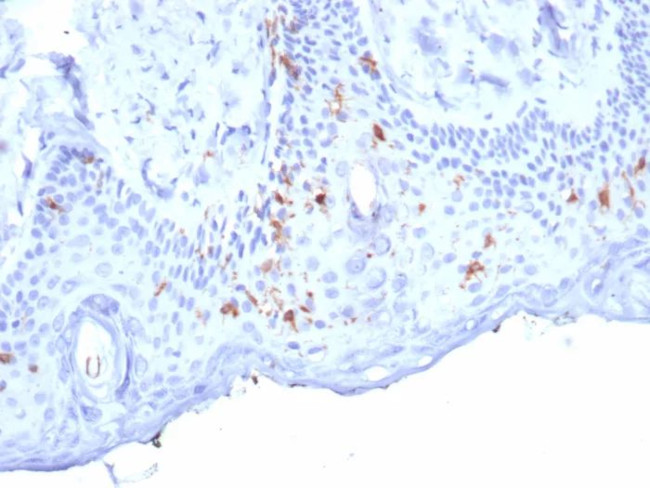

Langerin/CD207 (Marker of Langerhans Cells) Antibody in Immunohistochemistry (Paraffin) (IHC (P))

Langerin/CD207 (Marker of Langerhans Cells) Antibody (50489-MSM7-P1) in IHC (P)

Formalin-fixed, paraffin-embedded human skin stained with Langerin Mouse Monoclonal Antibody (LGRN/7357). HIER: Tris/EDTA, pH9.0, 45 min. 2°C: HRP-polymer, 30 min. DAB, 5 min. {{ $ctrl.currentElement.advancedVerification.fullName }} 验证信息 View more

Positive Control:Human skin.

Cellular Location: Cell Surface. Cytoplasm.

Langerin (CD207) is a type II membrane-associated C-type lectin known to be expressed exclusively by Langerhans cells. Lamgerin recognizes mannose residues via its single carbohydrate recognition domain (CRD). Langerin is localized not only on the cell surface, but also intracellularly in close association with Birbeck granules. Transfection of Langerin cDNA into fibroblasts creates a compact network of membrane structures with typical features of Birbeck granules (BG). Langerin is thus a potent inducer of membrane superimposition and zippering leading to BG formation.